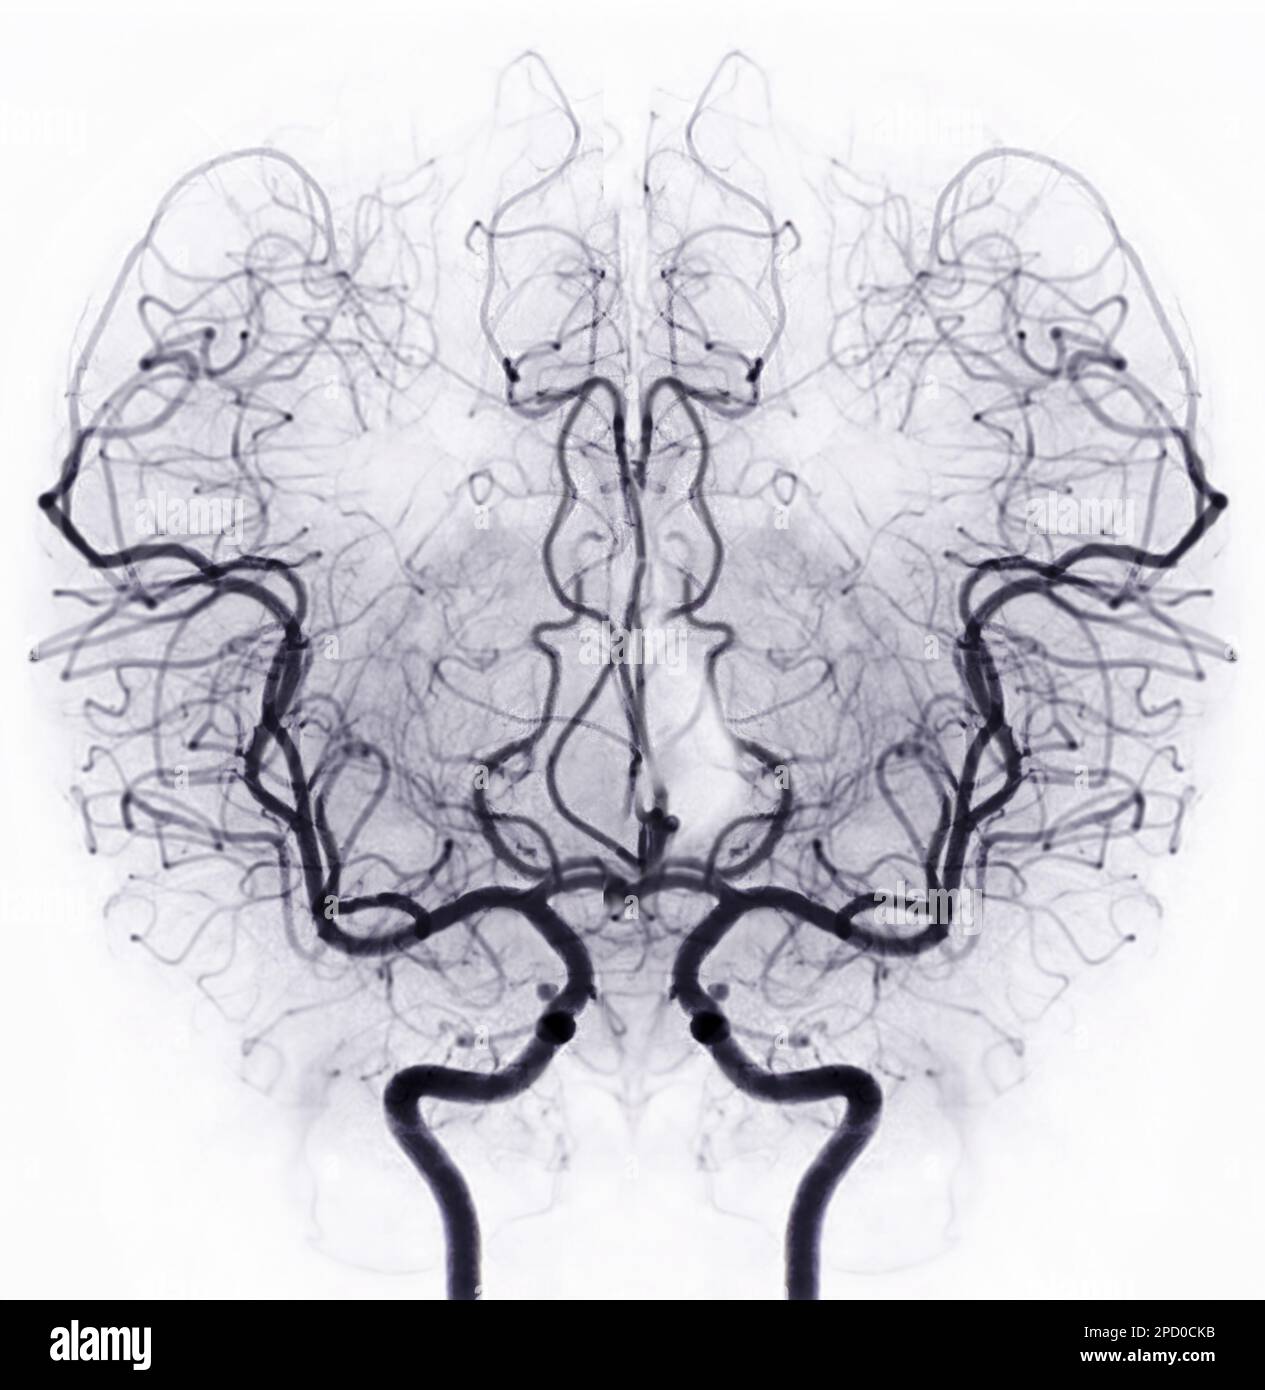

L'angiografia (da greco angeion per vaso e graphein per scrivere, rappresentare) è la rappresentazione a scopo diagnostico dei vasi sanguigni o linfatici del corpo umano tramite una tecnica che prevede l'infusione di un mezzo di contrasto idrosolubile all'interno dei vasi e la generazione di immagini mediche tramite varie tecniche di imaging biomedico.

Le tecniche angiografiche comprendono la radiografia (specificamente nella tecnica dell'angiografia sottrattiva, o DSA da Digital Subtraction Angiography), la tomografia computerizzata, la risonanza magnetica, l'ecografia.

Il neurologo portoghese Egas Moniz, vincitore del premio Nobel nel 1949, ideò nel 1927 la tecnica dell'angiografia cerebrale a raggi X con mezzo di contrasto per diagnosticare diversi tipi di disturbi nervosi, come tumori e malformazioni arterovenose. È generalmente riconosciuto come uno dei pionieri in questo campo.

Gli esami angiografici più comuni vengono tuttora ottenuti tramite raggi X e mezzi di contrasto radio-opachi. Questi ultimi si rendono necessari in quanto il sangue ha normalmente lo stesso coefficiente di attenuazione per le radiazioni X dei tessuti circostanti.

Normalmente, alle immagini evidenziate dal mezzo di contrasto viene sottratta un'immagine ottenuta prima dell'introduzione dell'agente di contrasto stesso, per rimuovere la contaminazione di strutture statiche dall'immagine che appariranno con la stessa intensità prima e dopo l'introduzione del mezzo di contrasto. Questa tecnica viene denominata angiografia sottrattiva o DSA (Digital Subtraction Angiography).